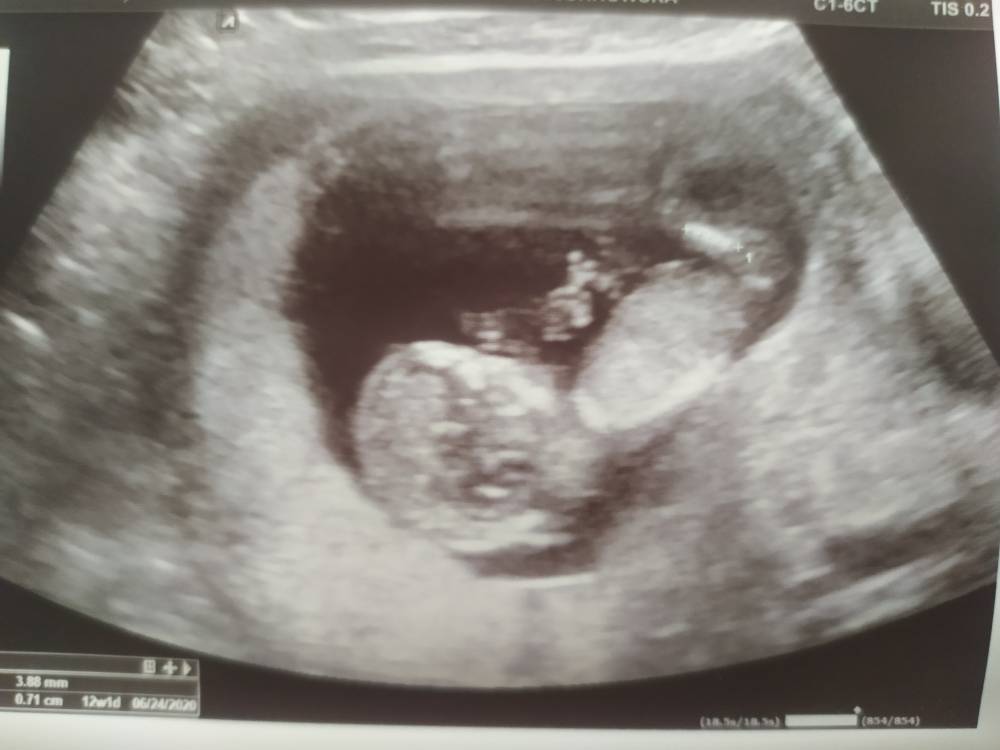

Dziewczyny tak jak piszecie obawy będą towarzyszyć nam przez całą ciążę. Ja jestem w 12 tyg dziś usłyszałam dobre nowiny byłam na badaniach prenatalnych i wszystko w porządku wyniki w normie maluch ma 5.1 cm w om a USG 1 dzień różnicy cudownie było patrzeć jak już fika, jak wkłada rączki do ust jak otwiera buźkę, łapie pępowinę. Ale stresa miałam dużego 2 ciąża skończyła się w 12 tyg. I czekałam na ten magiczny dla mnie moment i mam nadzieję że już do końca będzie dobrze. Ja testu Pappa nie robię w styczniu dostanę skierowanie na dodatkowe badanie echa serca bo ponoć teraz to standard, choć dziś wszystko było prawidłowo. Ponoć lekarz nieśmiało obstawia chlopca. Czytam te ciężkie rzeczy na forum i glupioi się cieszyć dziś własnym szczęściem ale ten dzień mi bardzo pomógł psychicznie.

Tp 24/25.06.2020 Zobacz załącznik 1056179Zobacz załącznik 1056180